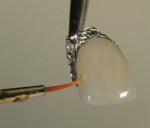

Once fired, the foil was carefully removed with tweezers (Figure 29). In this mirrored image, the author checked for the orange mamelon and calcification coloring. The gingival area had a slightly darker orange hue (Figure 30). Still, upon trying the restoration in the mouth, the author determined that the veneer needed color adjustment for a more lifelike appearance (Figure 31).